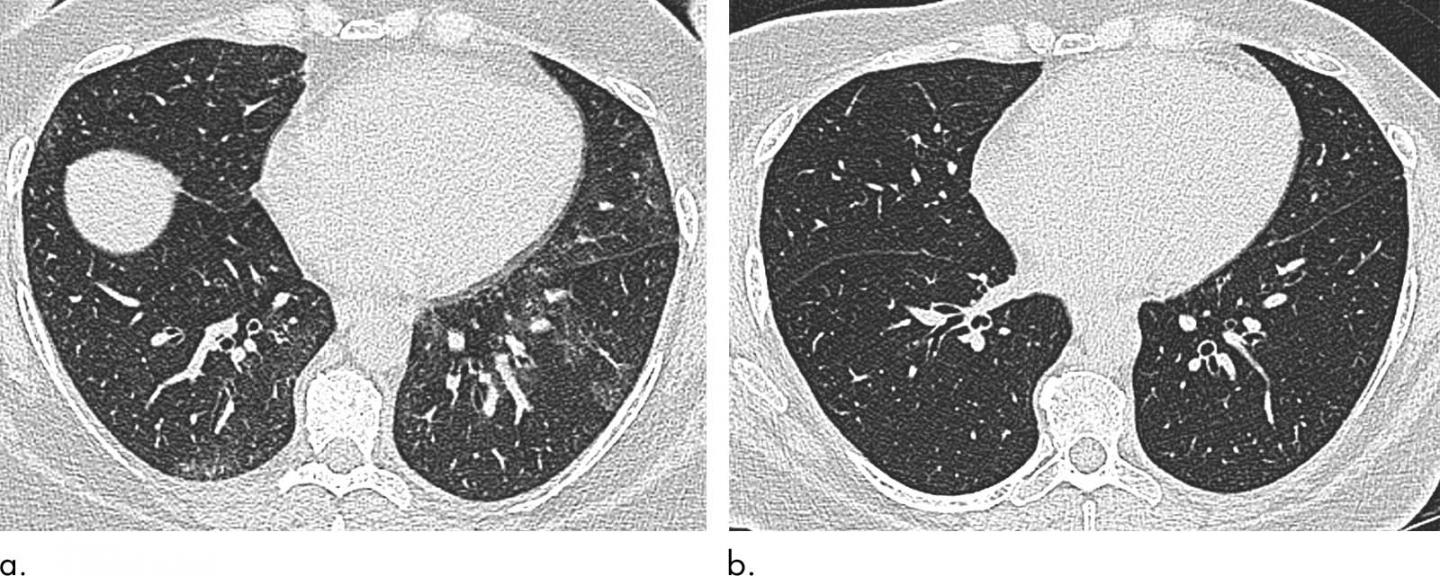

image: Axial unenhanced inspiratory CT images of the lungs in 51-year-old woman (a) before and (b) 6 months after bariatric surgery with 31-kg weight loss (body mass index decrease, 36.1%). The mosaic attenuation seen before surgery resolved after surgery.

When the researchers compared results at baseline and six months after bariatric surgery, they found that surgery and weight loss were associated with morphological, or structural, changes to the lung and trachea.

Post-surgery CT showed reductions in air trapping and a lower incidence of tracheal collapse. Change in the extent of CT air trapping was the strongest predictor of improvement in dyspnea, or shortness of breath.